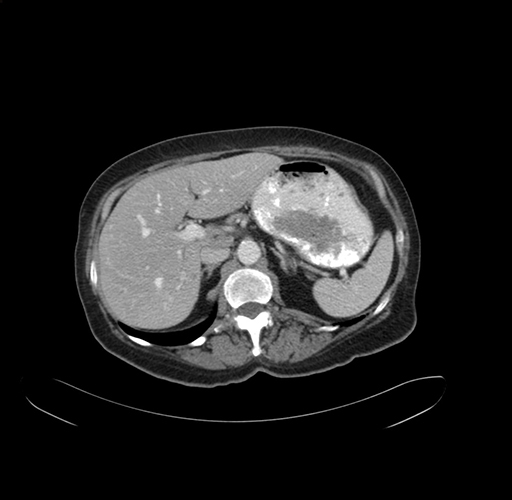

Pre-Chemo: Axial Venous

Pre-Chemo: Coronal Venous

Axial Venous

Coronal Venous

Imaging analysis

Based on your CT findings, which issue(s) would give reason for "planned slowing down moment(s)" in this case?

Considering a standard right hepatectomy procedure, what step(s) of the operation would you do differently in this case?